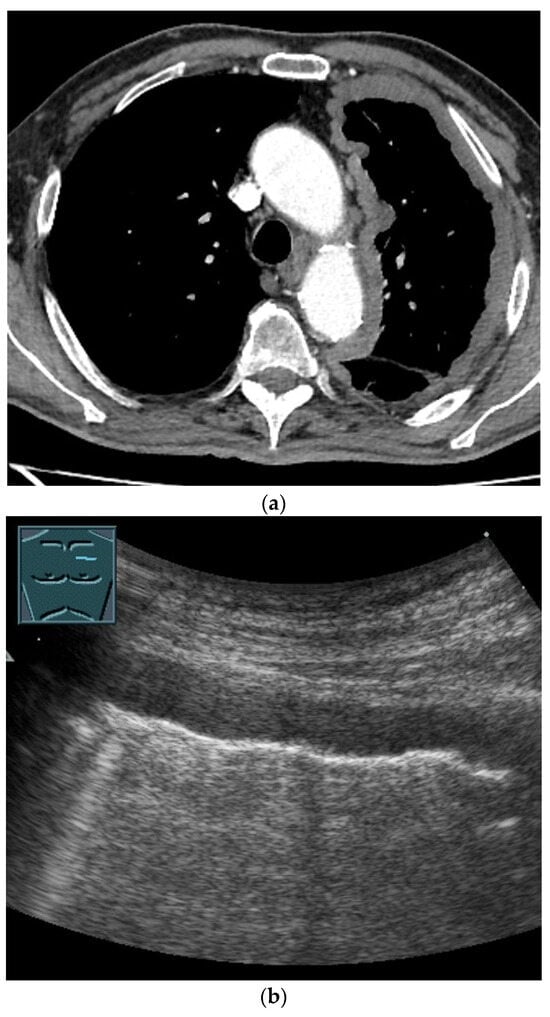

3. Pleural Mesothelioma